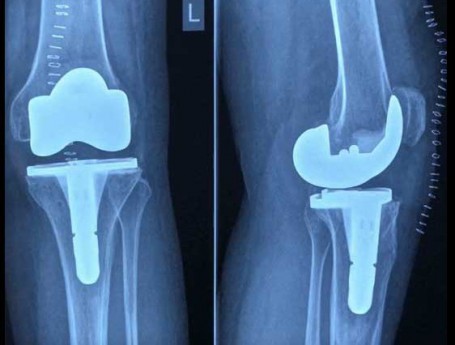

Total Knee Replacement